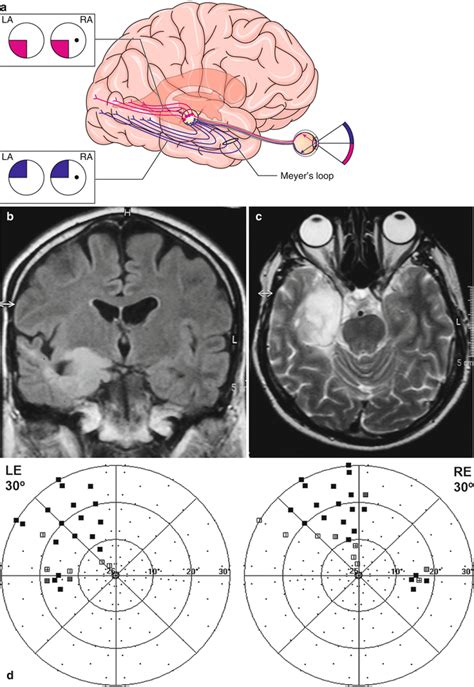

Title: - Homonymous Visual Field Defects